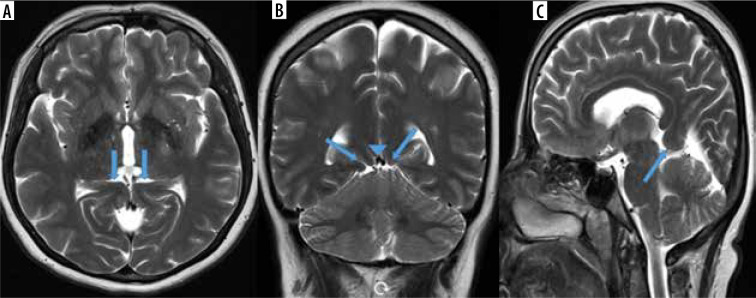

Purpose: The tent shape of the tentorium cerebelli helps preserve brain anatomy by providing cerebellum protection against pressure caused by the brain's gravity effect. In the absence of this support structure of the tentorium, herniation occurs in the brain. Isolated tentorial hypoplasia (TH) is extremely rare. In this study, we aimed to calculate the prevalence of this entity, which is reported to be rare in the literature.

Material and methods: Magnetic resonance imaging (MRI) images of 5163 patients who applied to the training and research hospital for various reasons between 1 September 2020, and 31 August 2021, who underwent brain MRI, were reviewed retrospectively.

Results: The prevalence of TH among patients screened during a period of one year was calculated as 2.22%. Of these, 76.59% were female (n = 72) and 23.41% were male (n = 22). The rates of presentation of complaints among TH patients were 60.63% headache, 17.02% vertigo, 4.25% seizures, 3.19% tremor, 3.19% syncope, 7.44% forgetfulness, and 2.12% visual impairment. Five patients (11.76%) were admitted for metastasis investigation due to their primary malignancy; they did not have any complaints. Localization of TH: 18.08% (n = 17) were observed on the right side, 28.72% (n = 27) on the left side, and 53.19% (n = 50) on the bilateral tentorium leaf.

Conclusions: Being aware of TH during brain MRI evaluation will help prevent possible misdiagnoses. We hope that this study with a large number of patients will increase awareness about TH, because there are no studies other than cadaver studies and a few case reports.